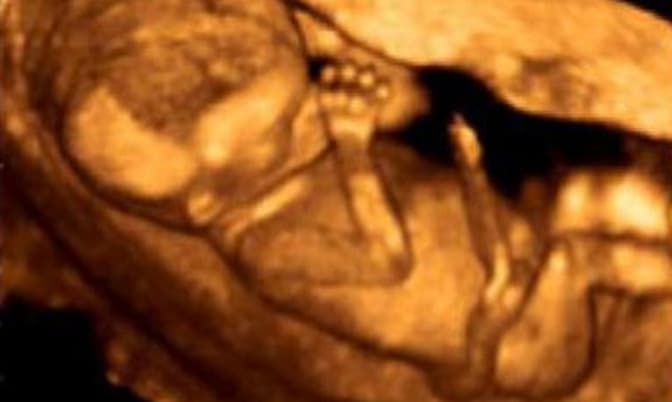

Materials to help your church speak out for the preborn, including sermon outlines and bulletin inserts.